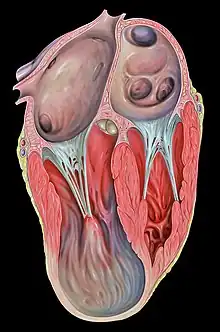

| Heart left ventricular aneurysm short axis view |

Ventricular aneurysms are one of the many complications that may occur after a heart attack. The word aneurysm refers to a bulge or 'pocketing' of the wall or lining of a vessel commonly occurring in the blood vessels at the base of the septum, or within the aorta. In the heart, they usually arise from a patch of weakened tissue in a ventricular wall, which swells into a bubble filled with blood.[1] This, in turn, may block the passageways leading out of the heart, leading to severely constricted blood flow to the body. Ventricular aneurysms can be fatal. They are usually non-rupturing because they are lined by scar tissue.

Ventricular aneurysms usually grow at a very slow pace, but can still pose problems. Usually, this type of aneurysm grows in the left ventricle. This bubble has the potential to block blood flow to the rest of the body, and thus limit the patient's stamina. In other cases, a similarly developed pseudoaneurysm ("false aneurysm") may burst, sometimes resulting in the death of the patient. Also, blood clots may form on the inside of ventricular aneurysms, and form embolisms. If such a clot escapes from the aneurysm, it will be moved in the circulation throughout the body. If it gets stuck inside a blood vessel, it may cause ischemia in a limb, a painful condition that can lead to reduced movement and tissue death in the limb.[1] Alternatively, if a clot blocks a vessel going to the brain, it can cause a stroke. In certain cases, ventricular aneurysms cause ventricular failure or arrythmia. At this stage, treatment is necessary.

Ventricular aneurysms are usually complications resulting from a heart attack. When the heart muscle (cardiac muscle) partially dies during a heart attack, a layer of muscle may survive, and, being severely weakened, start to become an aneurysm. Blood may flow into the surrounding dead muscle and inflate the weakened flap of muscle into a bubble. It may also be congenital.